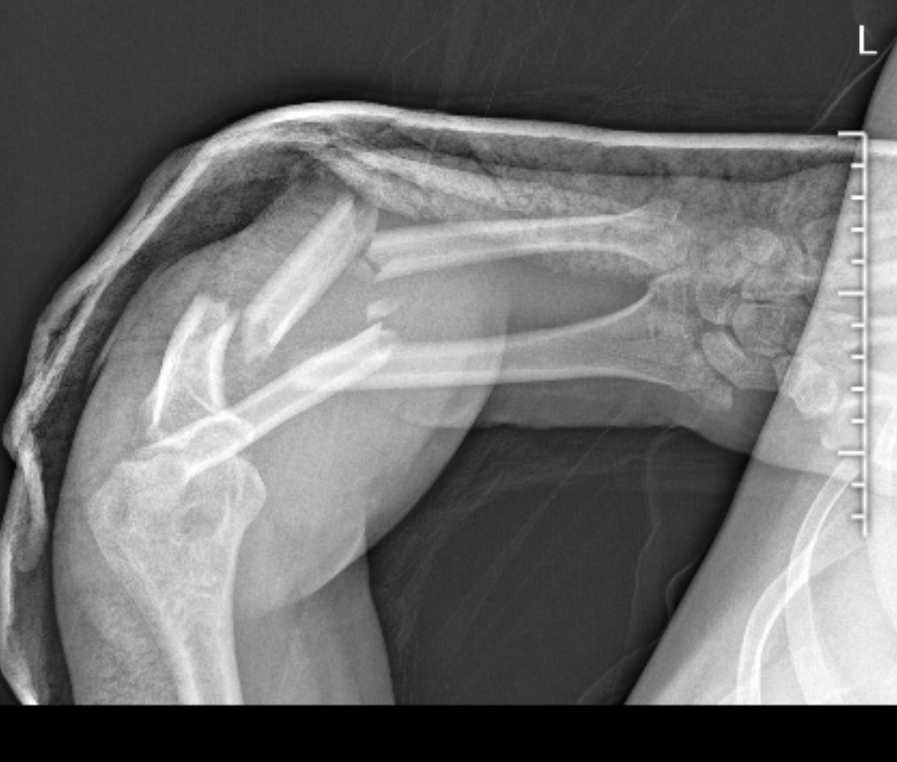

去年这时候尺桡骨粉碎性骨折,在第一家医院还出了医疗事故,有处骨折未发现,钢板打得也不好,术后一个月换了家医院拆开钢板,做翻新修复。术后经历了3个月生不如死的康复,目前一年了,复查完一切正常,等骨头再长半年就可以拆钢板了。。第一家医院医生还说我肯定会残疾,手臂以后没法旋转。。

而且伤口没增生,万幸。。订了锦旗送第二个医生。。